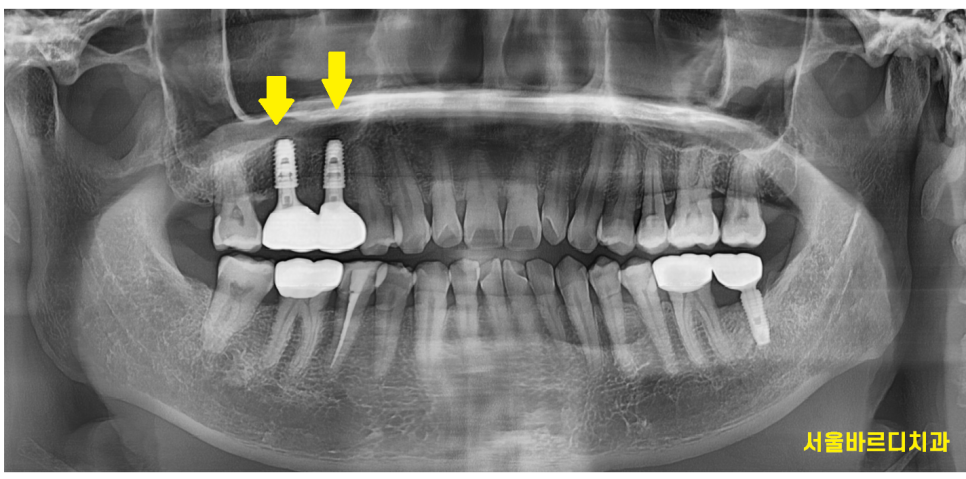

x-ray를 통하여 검사를 해보니

잇몸뼈가 전반적으로 내려가있습니다.

특히나 윗니 양쪽 어금니 부분이 많이 내려가 있으며

230320

오른쪽 윗니 어금니 2개 상태가 많이 안좋습니다.

뿌리쪽에 고름이 있어서

잇몸뼈가 많이 녹았는지 주변보다 까맣게 보입니다.